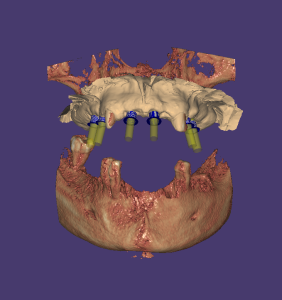

Curso Exoplan PRO

Curso Exoplan BASIC (Incluido)

Técnica Doble Dicom

Técnica Dicom Stl

Curso Flujo Exocad / Exoplan

Curso integración avanzado para dentistas (incluido)

Curso Exoplan PRO (incluido)

Dirigido a Dentistas los cuales quieran realizar la planificación y diseño del encerado, colocación de implantes Full Mouth y carga inmediata o diferida.

- Cirugías presenciales con planificación digital

- Implantología básica e inmediata

- Pilares personalizados y posicionadores

- Full mouth con carga inmediata o diferida

Curso Bluesky Plan Avanzado

Requiere Curso Bluesky Plan Básico o manejo demostrable Diseño y colocación de implantes / Fabricación de guía quirúrgica Pilares personalizados y posicionadores Técnica Doble Dicom / Técnica Dicom Stl Guia de recorte óseo https://www.blueskyplan.com/...